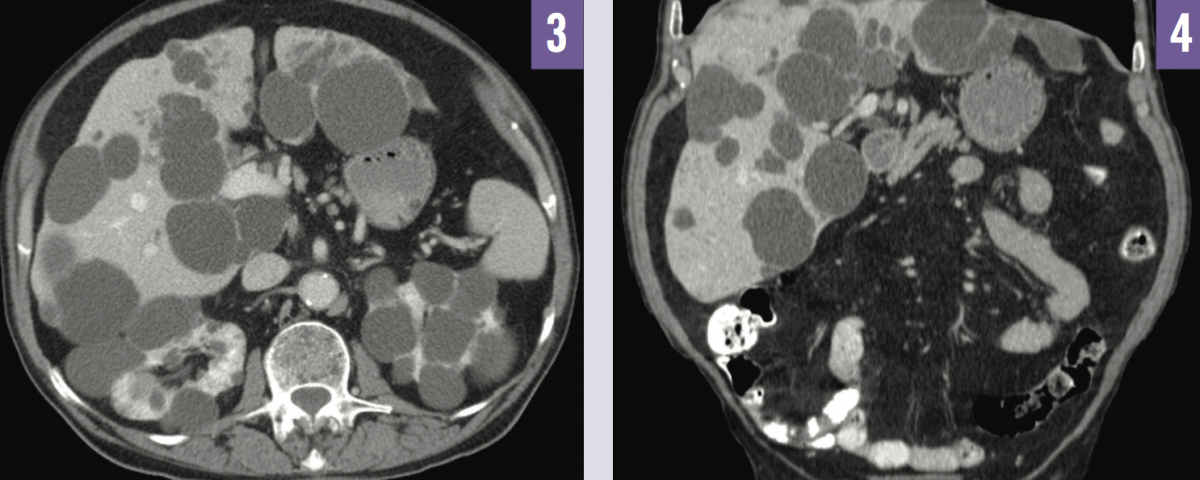

Abdominal ultrasonography demonstrated bilateral enlarged kidneys with several cysts of varying size (Figure 1), and multiple scattered echo-dense cysts measuring up to 7 cm throughout the liver (Figure 2). Noncontrast computed tomography (CT) imaging showed numerous hepatic cysts in association with bilateral kidney cysts (Figures 3 and 4). These findings were compatible with a radiographic diagnosis of autosomal dominant polycystic kidney disease (ADPKD).